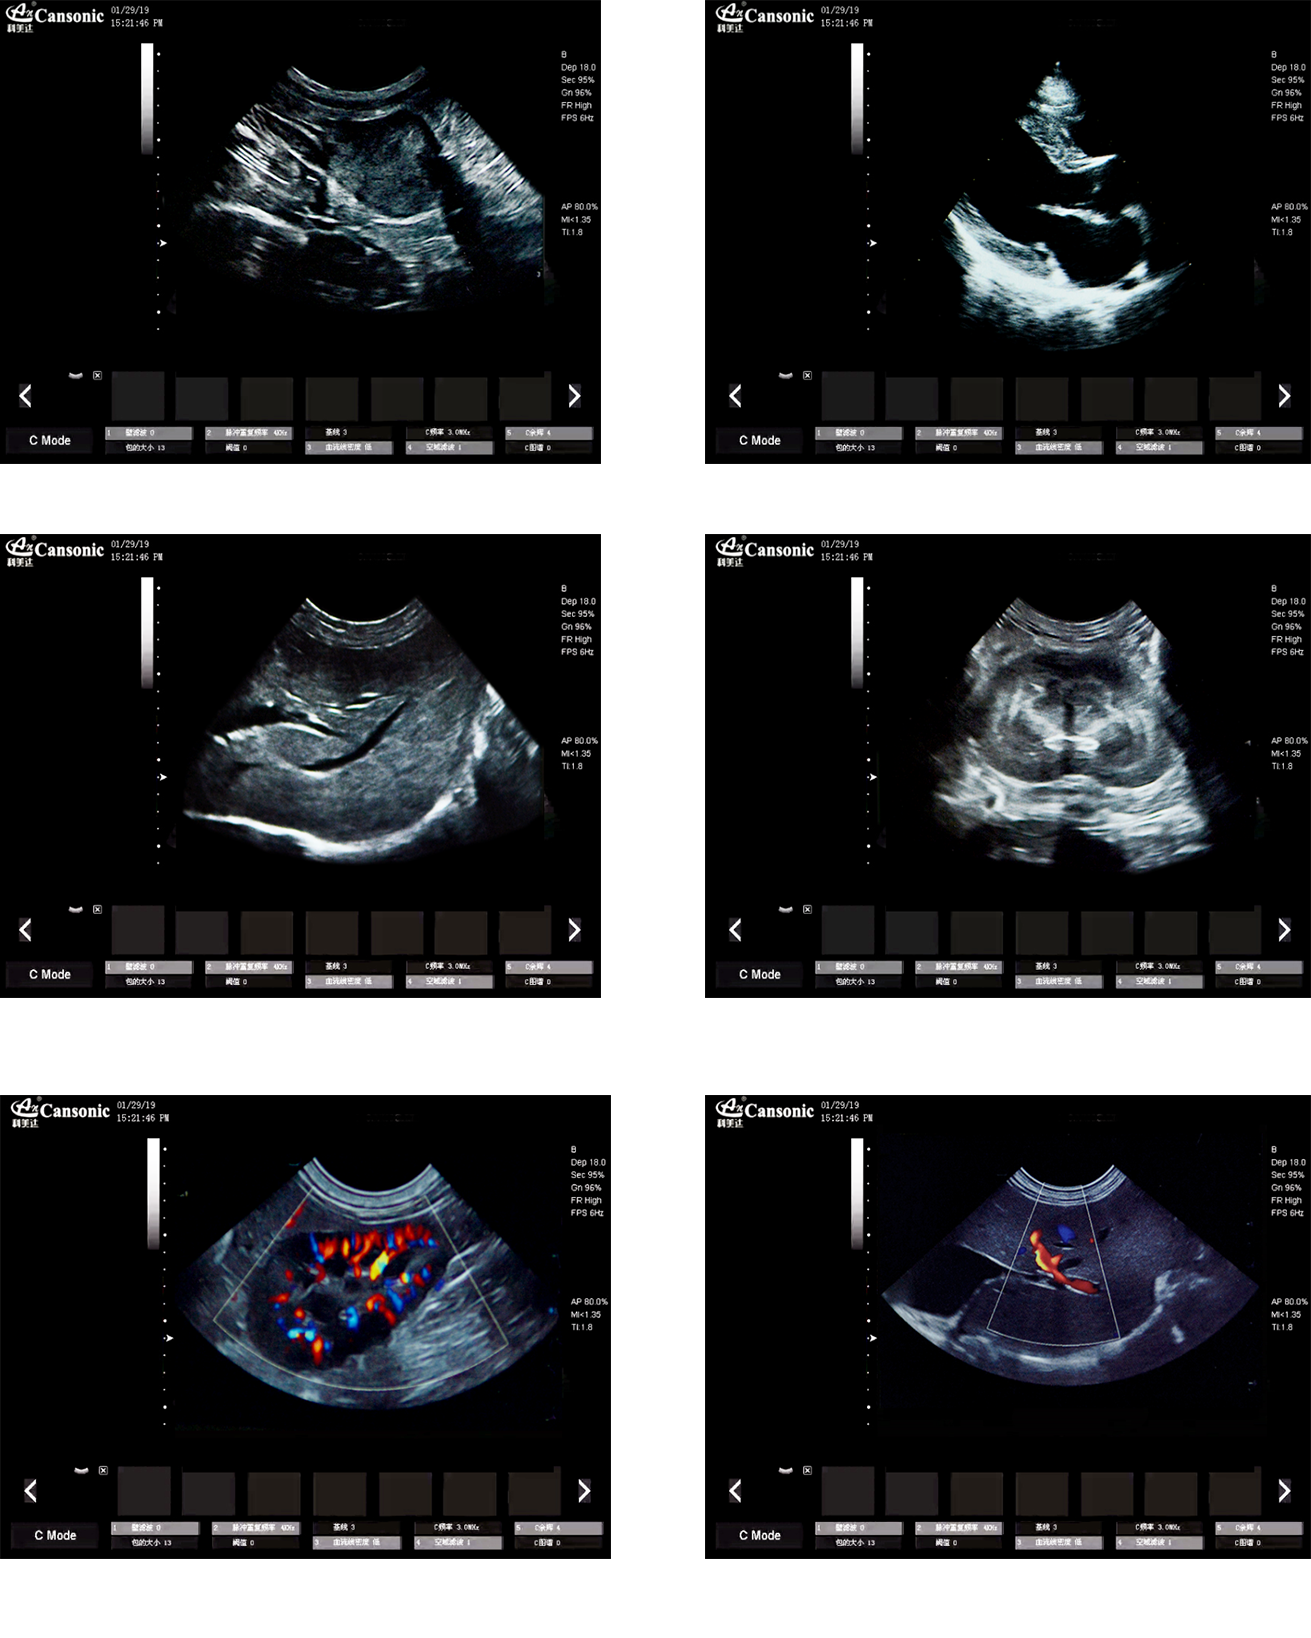

臨床圖示